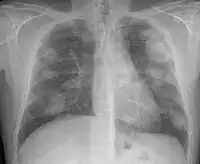

Complicated silicosis

Silicosis ILO Classification 2-2 R-R

Fibrothorax and pleural effusion caused by silicosis